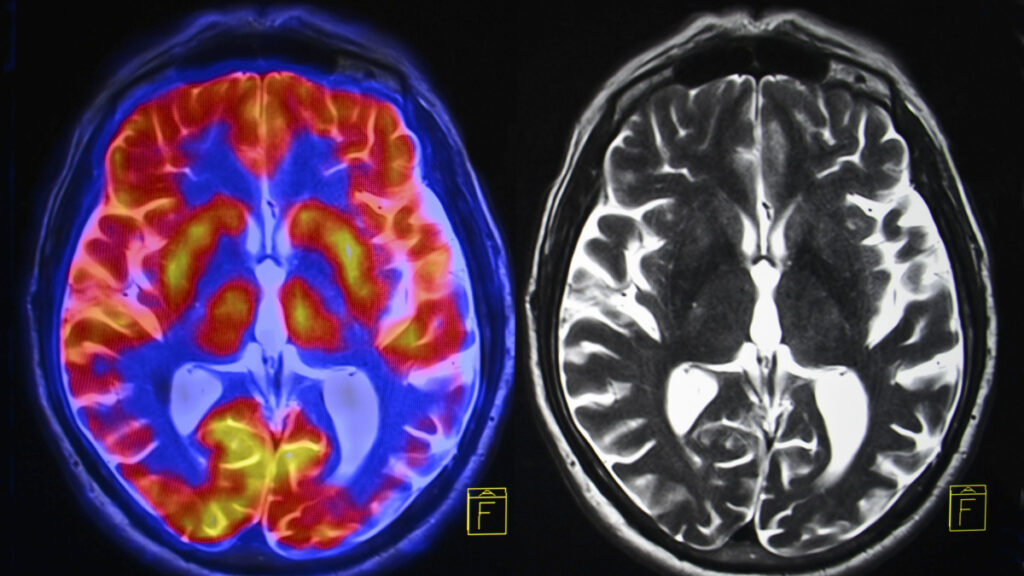

MADRID – Las complicaciones

neurológicas de la covid-19 pueden incluir delirio, daño nervioso, derrames y

un raro tipo de inflamación cerebral, aunque los investigadores no tienen

claro, en este último caso, si es producto del coronavirus o de la reacción

inmunitaria, según un estudio que publica la revista Brain.